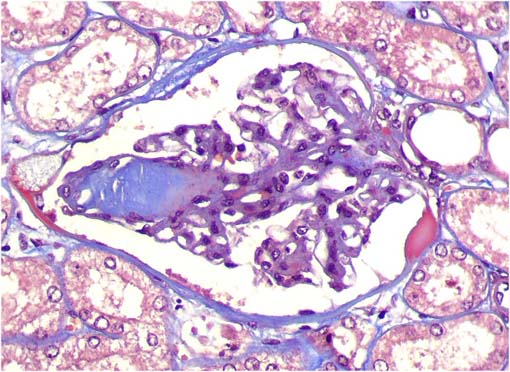

Figura 4.

Tricrómico de Masson, X400.